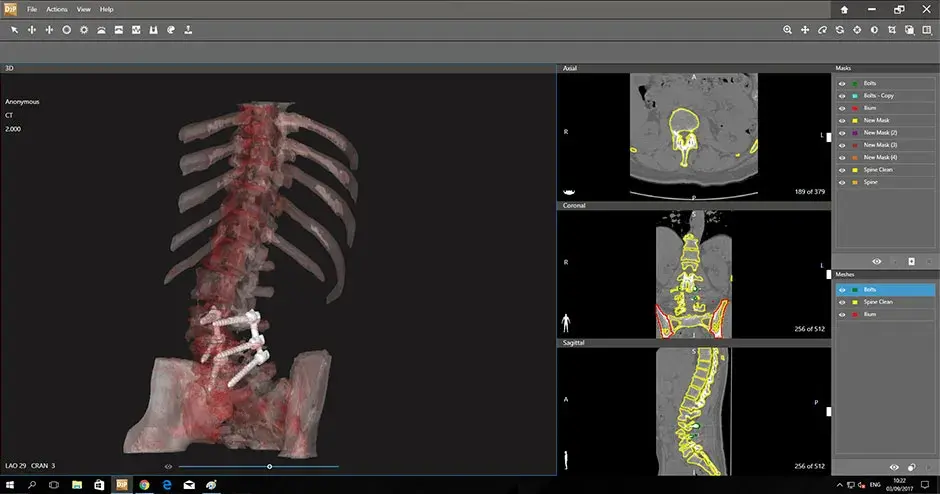

3D Systems partners with device manufacturers and healthcare providers to transform surgical outcomes for both patients and surgeons. We create custom solutions that help translate virtual surgery into the OR with the goal of improving outcomes and the overall patient experience. Our multifaceted offerings include advanced design and planning software, expert planning services and a full range of custom implants and instrumentation.